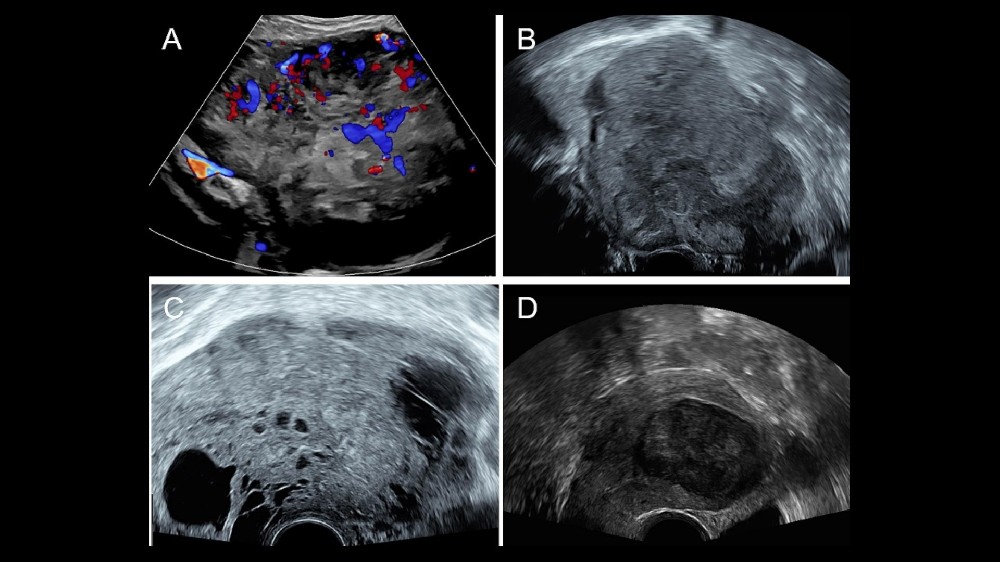

由於這些症狀都是非特異性的,因此準確的診斷需要專家的檢查,通常會使用超音波和先進的影像技術 (MRI 或 CT 掃描)。

子宮肉瘤 (Uterine Leiomyosarcoma) 常常會呈現細微的症狀,一開始可能會被誤以為是良性的婦科問題。及早發現這些症狀對提高成功治療的可能性至關重要。瞭解這些獨特和常見的症狀,可以及時進行醫療評估和介入治療。

由於這些症狀也類似纖維瘤等不太嚴重的疾病,因此許多婦女一開始都會忽略這些症狀。因此,持續警覺和及時就診是非常重要的,尤其是對於症狀持續或惡化的患者。早期發現可顯著改善子宮線肉瘤的預後及治療方案。